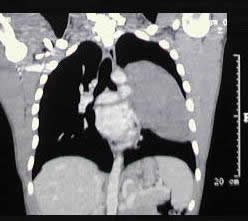

un paciente joven, con un gran tumor del mediastino anterosuperior de rápido

crecimiento, correlacionando su tamaño entre la radiografía

del tórax y los hallazgos tomográficos realizado 15 días

después, y las condiciones físicas al momento de su intervención,

con gran dificultad respiratoria.